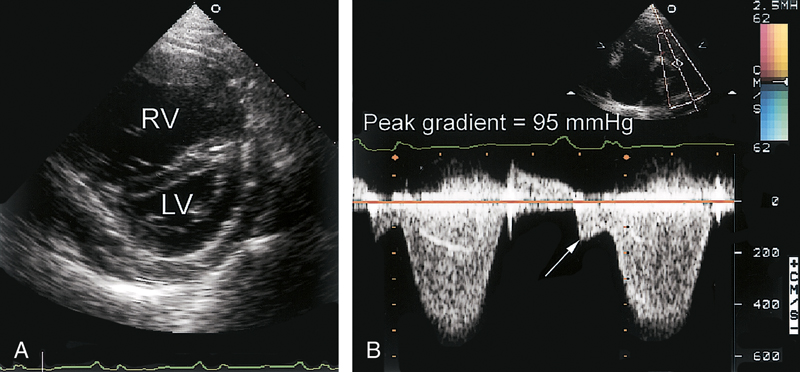

فحوصات تشخيصية لبعض امراض القلب والشرايين التاجية